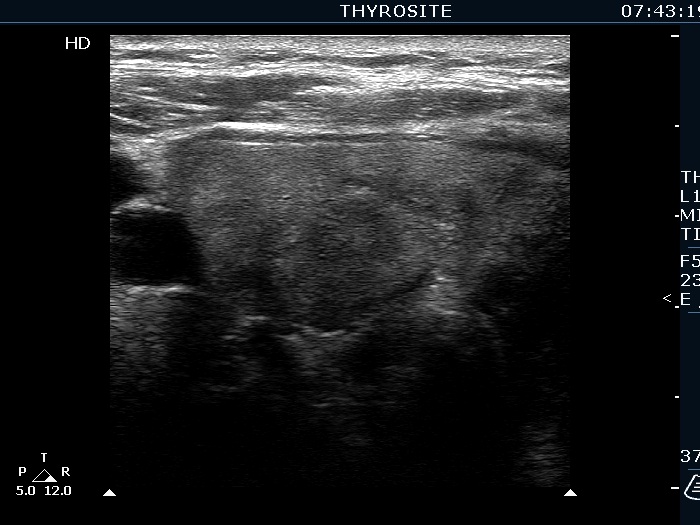

Ultrasonography. The right lobe was echonormal and presented several hypoechoic nodules. A large, inhomogeneous, partly deeply hypoechoic, partly minimally hypoechoic or echonormal mass occupied the left lobe. The borders of the tumor were irregular. There were multiple lymph nodules upper and lateral to the left thyroid lobe. The nodes had a heterogeneous pattern and lacked hilum. The vascularity was scanty both in the thyroid nodules and the lymph nodes.